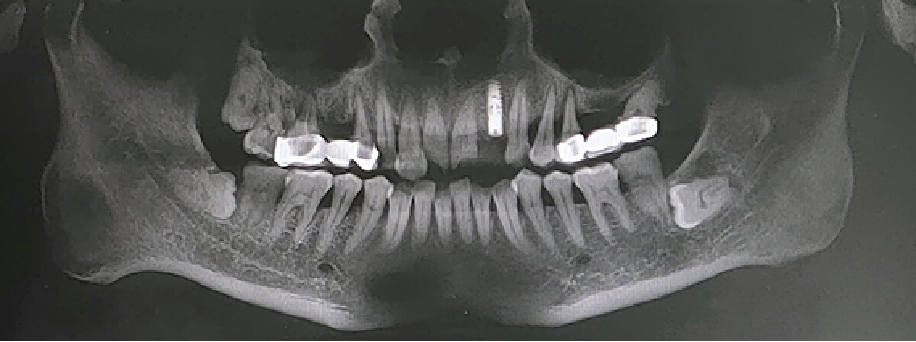

术前CBCT

21颊侧牙槽骨吸收至根尖,腭侧牙槽骨吸收至根尖1/3,根周可见低密度影。牙槽嵴宽度6.41mm。

局部反合、患牙长期牙周病变,骨质缺损,但软组织无明显缺失,为II类拔牙窝形态。

22冠状位CBCT情况

唇舌牙槽嵴宽度6.41mm,垂直骨缺失1/2,软组织无垂直向缺失。